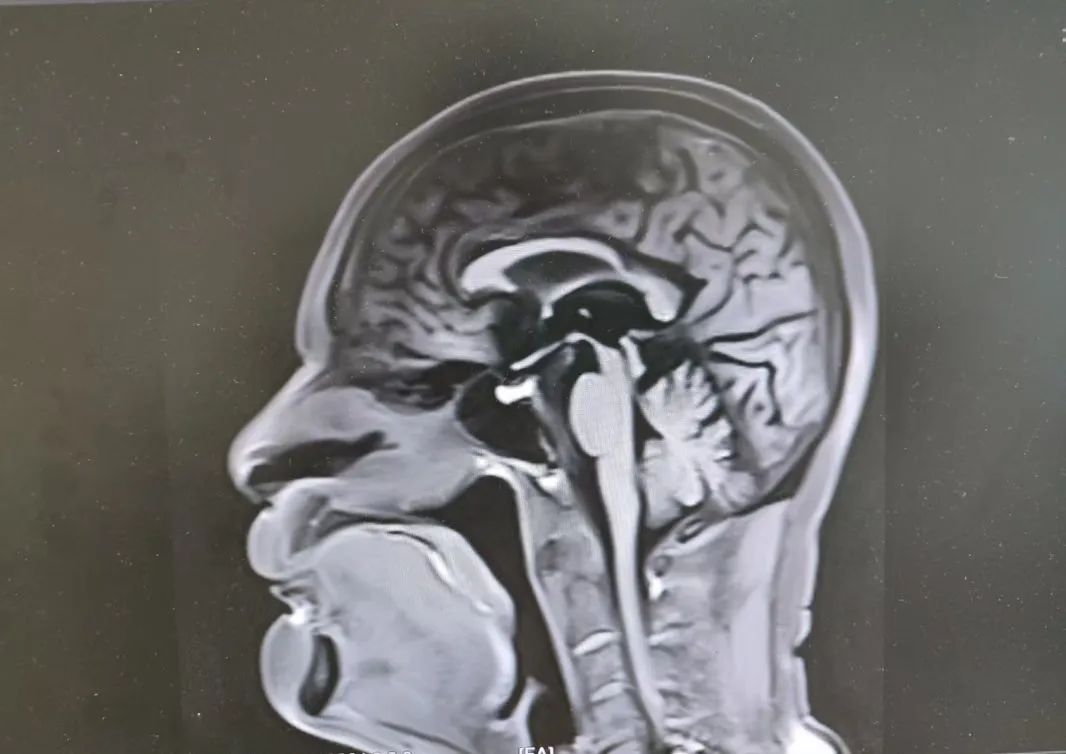

81岁的李大爷(化名),一年前开始右侧肢体不灵,走路向后倾斜,期间经常跌倒,随着症状逐渐加重,家属赶紧带着老人找到赵智江教授。入院后,赵智江教授发现患者存在肌张力增高、运动迟缓、站立时向后倾倒、眼球垂直运动障碍等症状,脑部核磁发现特征性“蜂鸟征”图像,结合相关血液检验结果,排除帕金森综合征和僵人综合征等干扰,确诊为进行性核上性麻痹(PSP)。

患者核磁“蜂鸟征”影像

进行性核上性麻痹是帕金森叠加综合征之一,多发于中老年人,容易被忽视或误诊为帕金森病。此次明确诊断,为李大爷的治疗指明了方向,对提高李大爷的生活质量起到了重要作用。